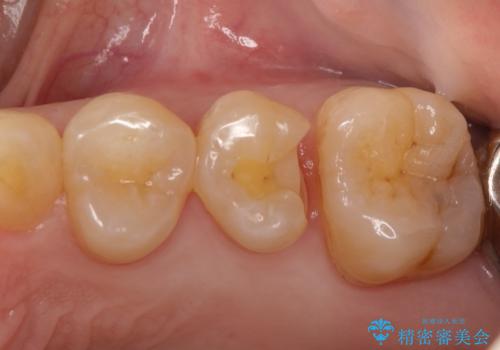

虫歯の治療。ゴールドインレーによる治療

- 定期検診にて、虫歯を発見した患者様です。

長期に安定した治療を希望されたためPGAインレーにて修復治療を行っております。

ゴールドインレーは適合が良く、割れることもないため、長期的に安定した治療法となります。